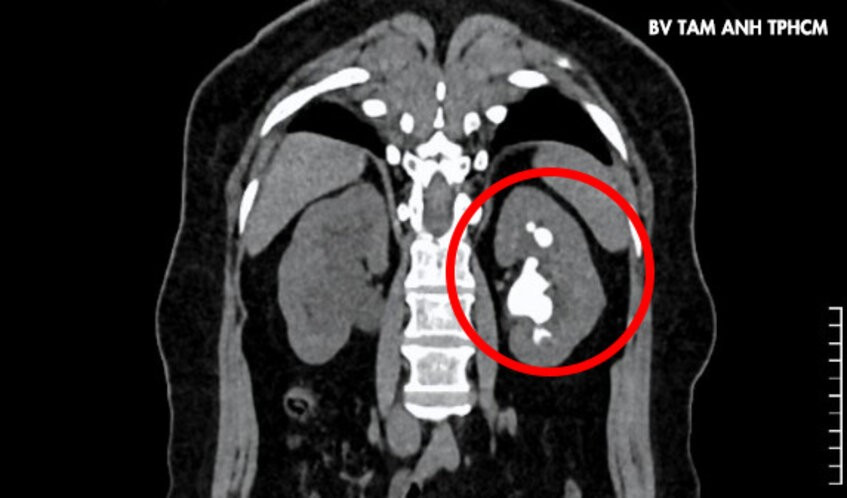

Sỏi san hô cứng, kích thước lớn (màu trắng trong hình tròn đỏ) ở thận trái gây đau đớn cho người bệnh. Ảnh: BVCC

Lên cơn đau quặn thận, bà Trinh, 51 tuổi, ngụ TP HCM đến Bệnh viện Đa khoa Tâm Anh TP HCM khám, bác sĩ phát hiện người bệnh có sỏi cùng lúc ở đoạn trên niệu quản phải, kích thước khoảng 8×10 mm. Thận trái có sỏi kích thước 24×42 mm cùng nhiều sỏi nhỏ ở đài thận trên.

ThS.BS Nguyễn Tân Cương, Phó khoa Tiết niệu, Trung tâm Tiết niệu – Thận học – Nam khoa, cho biết sỏi thận trái có hình dạng san hô lấp đầy các đài thận, nguy cơ nhiễm khuẩn và tổn thương thận một cách âm thầm, người bệnh cần phẫu thuật sớm.